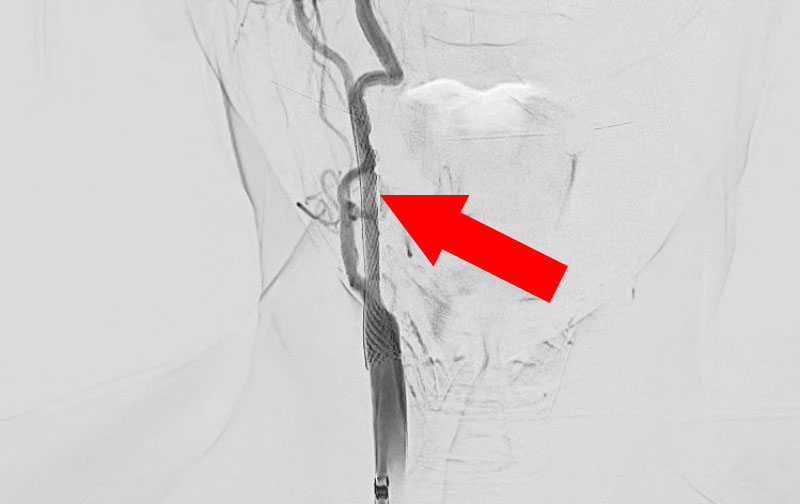

1350

'23年2月27日

右内頚動脈狭窄症

70代

大阪府の病院

手術写真

治療

前

中

後

手術日